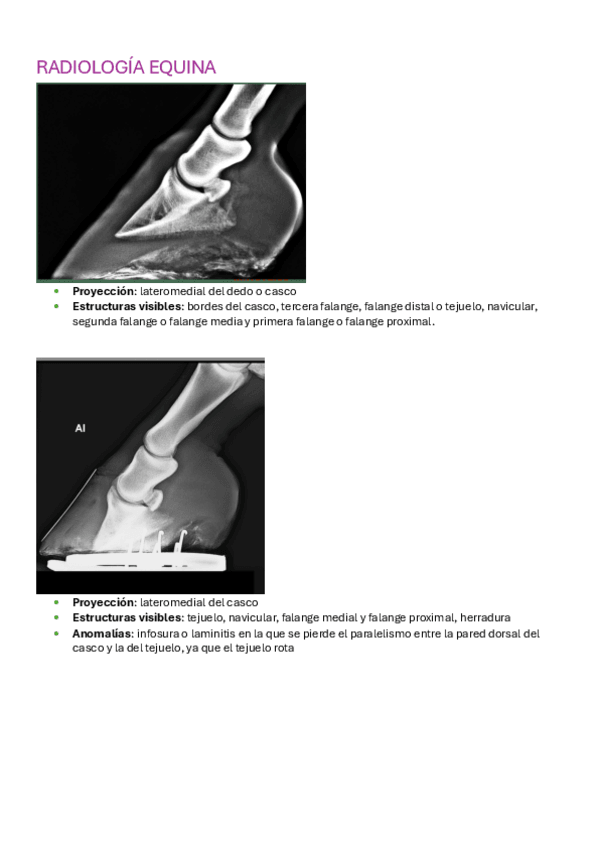

Imágenes de radiografias explicadas

He publicado nuevos apuntes de 3º Diagnóstico Por la Imagen: Imágenes de radiografias explicadas

Rx-equina-1.pdf